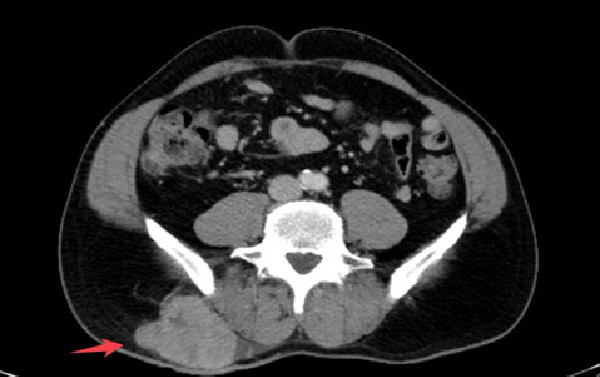

65歲W先生偶然在右下背摸到一個不痛不癢的小腫塊,原想著過些時日再去醫院掛號做檢查,沒想到這個小腫塊卻迅速長大,三個月內像吹汽球似的長到了7公分大,到新竹臺大分院新竹醫院就診,經檢查診斷是惡性軟組織肉瘤。

新竹臺大分院整形外科張晏誠醫師說明,惡性軟組織肉瘤是癌症的一種,約佔所有癌症診斷的 1%,算是一種較少見的癌症。惡性軟組織肉瘤一開始最常表現為四肢或軀幹的增大、無痛的腫塊,最常被診斷於50-60歲左右,男性稍多於女性。在初步診斷時出現遠端轉移的情況並不常見,但在大型、深部的肉瘤中就有可能發生,而大約有80%的轉移發生在肺部。

張醫師表示,惡性軟組織肉瘤在初期可能沒有特定的症狀,直到腫瘤增大並對周圍組織造成侵犯或壓迫,才可能引發神經疼痛或器官受壓症狀。此時,腫瘤體積通常已經相當巨大,使得手術難以完全切除,造成治療上的挑戰。一般而言,約有50%的惡性軟組織肉瘤發生在四肢,20%生長在軀幹,另外約有9%生長在頭頸部。針對惡性軟組織肉瘤的治療原則,主要是以手術切除為主,手術後可能需要進行輔助性放射治療以增強治療效果。若腫瘤發生在四肢部位,通常較容易實現完整切除,但如果腫瘤體積過大,或位於難以完全清除的區域,則可考慮先行輔助性化學治療以縮小腫瘤體積,之後再進行手術切除。